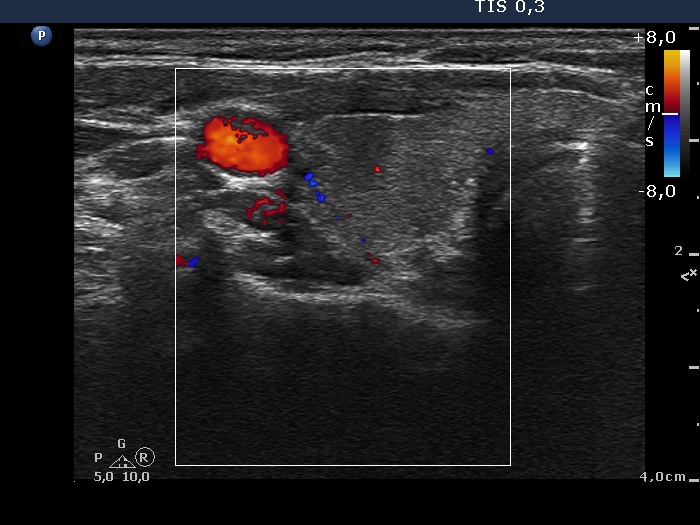

Initial examination (first row of images):

Ultrasonography: The thyroid presented with hypoechoic areas which had blurred borders. The echogenicity index was approximately 65% in the right and 20% in the left lobe. The thyroid was almost completely avascular.